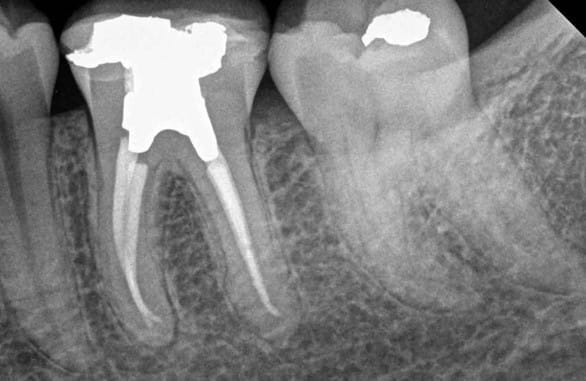

Patient presented one year after treatment and post-op x-ray reveals successful root canal treatment and healing.